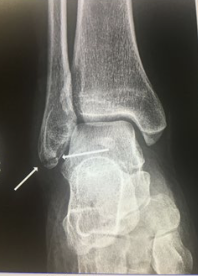

What type of fracture is this?

Avulsion

What is an avulsion fracture?

Fragment of bone is pulled away an attached tendon or ligament